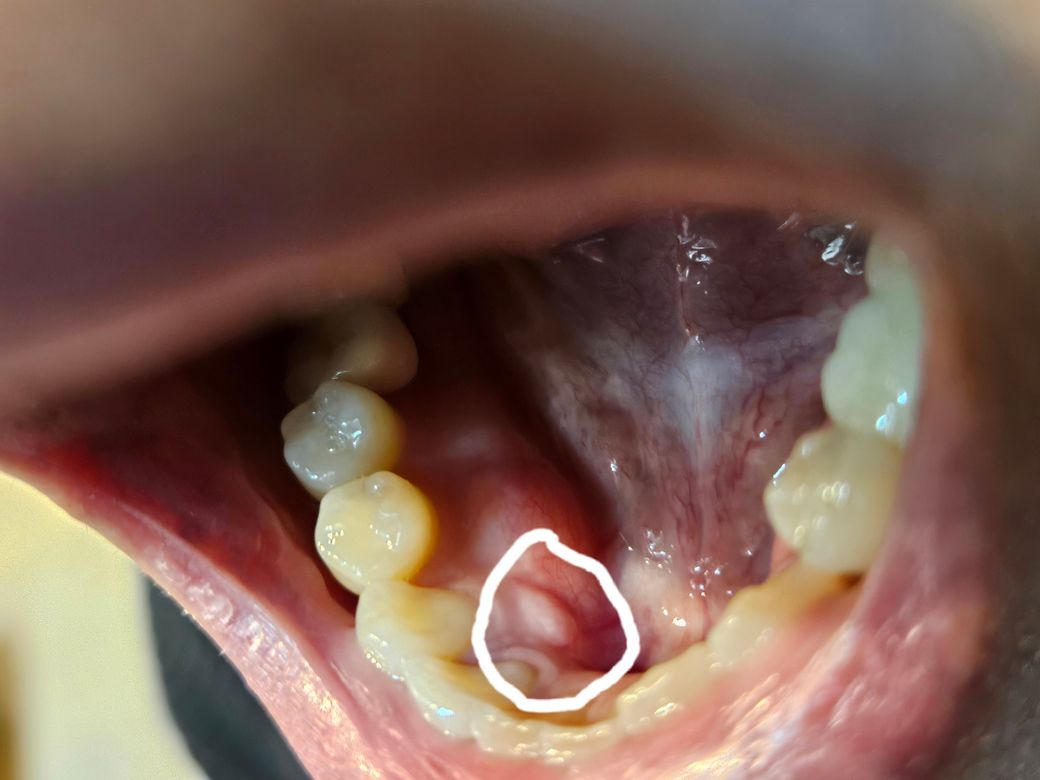

입안 아랫니 안쪽잇몸에 이거 멀까요??

지난번 우연히 안쪽을봣는데 허옇게 허른?거 처럼 생겻더라구요 짐 몇주지난거같은데 그대로인데 통증은 전혀없구요 이런증상 잇으셧던분 ㄱㅖ실까요

• 1번 째 사진

치아를 감싸고 있는 치조골이 밖으로 자라나온 것으로 보입니다 견고한 느낌이 든다면 단순하게 뼈가 있는 것이기 때문에 큰 문제가 아닐 가능성이 높습니다 자세한 확인을 위해서 치과에서 진료를 받아 보는 것을 권유 드립니다.

• 사진상 보이기로는 잇몸 부위 염증의 양상입니다 통증은 없더라도 치과에가서 잇몸 그리고 주변치아에 대한 진단을 한번 받아보시기 바랍니다